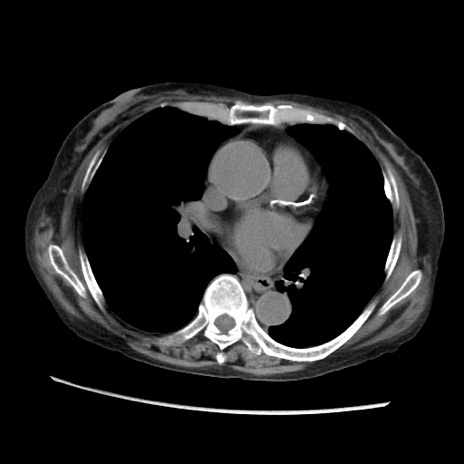

症例31(横断像)

【症例】80歳代 女性

【主訴】腹部膨満感

【現病歴】他院にて肝硬変にてフォロー中。1週間前から便秘、腹部膨満感、臍部腫瘤あり受診となる。

【既往歴】肝硬変

【身体所見】腹部膨隆あり、皮膚変化なし、疼痛なし。

【データ】WBC 4600、CRP 0.25